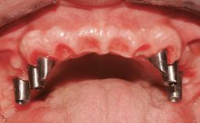

Fixed and removable prosthodontic implant therapy for restoration of the edentulous maxilla is both complex and challenging. Careful assessment and planning is needed in each individual case to explore whether a fixed or a removable solution will be the more suitable to satisfy the patient’s preference for optimal esthetics, phonetics, comfort and function. This Learning Pathway explores the prosthodontically driven treatment planning based on structured assessment, considered diagnosis and practical application in clinical case examples.